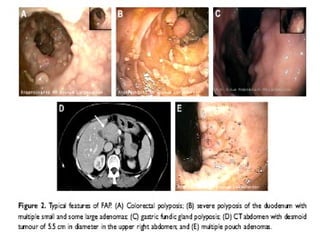

Poliposis Adenomatosa Familiar Manifestaciones extracolonicas: Hipertrofia congénita de la retina. Osteomas. Odontomas Quistes epidermoides. Se asocia a neoplasias de páncreas, árbol biliar, gástricas, intestino delgado. Hay pólipos gástricos, duodenales y periampulares. Best Practice & Research Clinical Gastroenterology Vol. 21, No. 3, pp. 409e426, 2007

Poliposis Adenomatosa FamiliarLos pólipos pueden tapizar toda la superficie del epitelio colorrectal en casos severos y dejar indemne algunas porciones del epitelio. La mayoría mide menos de 5 y 10 mm. El hallazgo de uno o más pólipos de más de 1 cm. se asocia a 47 % de padecer CCR. La mayoría de PAF. Presentan CCR. de localización izquierda o distal. La frecuencia de neoplasias sincrónicas o metacrónicas es elevada..colectomía total. Best Practice & Research Clinical Gastroenterology Vol. 21, No. 3, pp. 409e426, 2007

Poliposis Adenomatosa FamiliarManifestaciones extracolonicas: Hipertrofia congénita de la retina. Osteomas. Odontomas Quistes epidermoides. Se asocia a neoplasias de páncreas, árbol biliar, gástricas, intestino delgado. Hay pólipos gástricos, duodenales y periampulares. Best Practice & Research Clinical Gastroenterology Vol. 21, No. 3, pp. 409e426, 2007